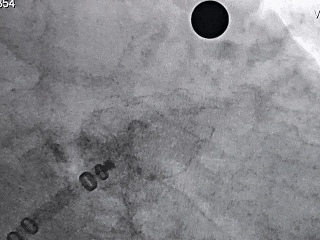

MemoLefort封堵器展开后DSA下充分评估

释放后DSA下造影,多切面观察封堵左心耳开口无残余分流,且封堵器放置位置理想,充盈整个心耳开口处。

右肩位牵拉有回弹,

器械稳定

压缩比12.4%,

在10%-30%之间,

符合推荐压缩比

同时肝位、右肩位造影确认封堵器位置合适,无残余漏,左心耳完全封堵